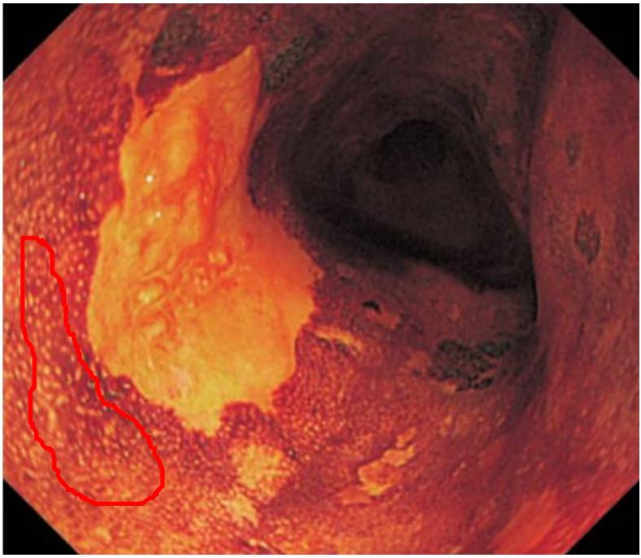

食管白斑

食管白斑,发生在我们食管内的疾病,应尽早治愈避免引发其它病变

食管白斑,发生在我们食管内的疾病 01 关于食管白斑的介绍 食管白斑